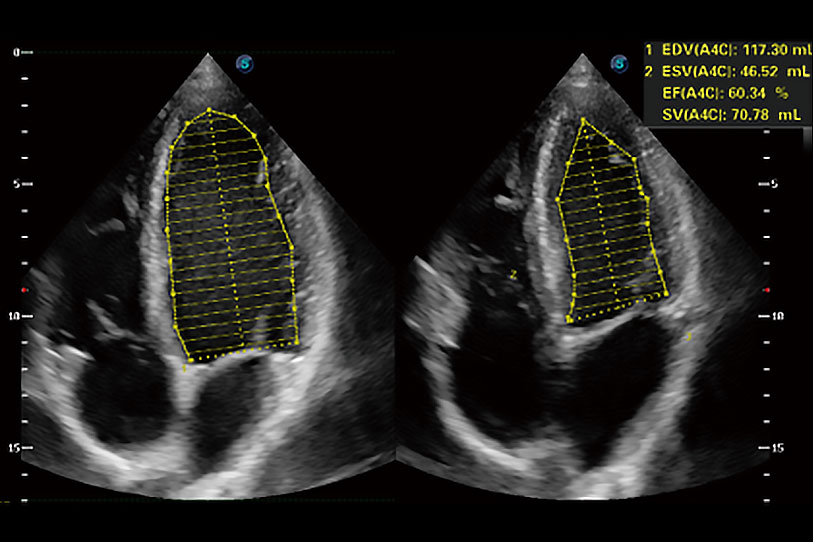

能够基于左心室壁追踪和辛普森法,自动计算射血分数,支持多个可移动点描迹,与手动测量相比,极大节省了动物医生的时间和精力。